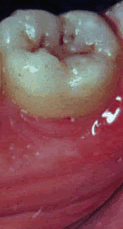

Pase el ratón para ver bolsa, recesión y movilidad